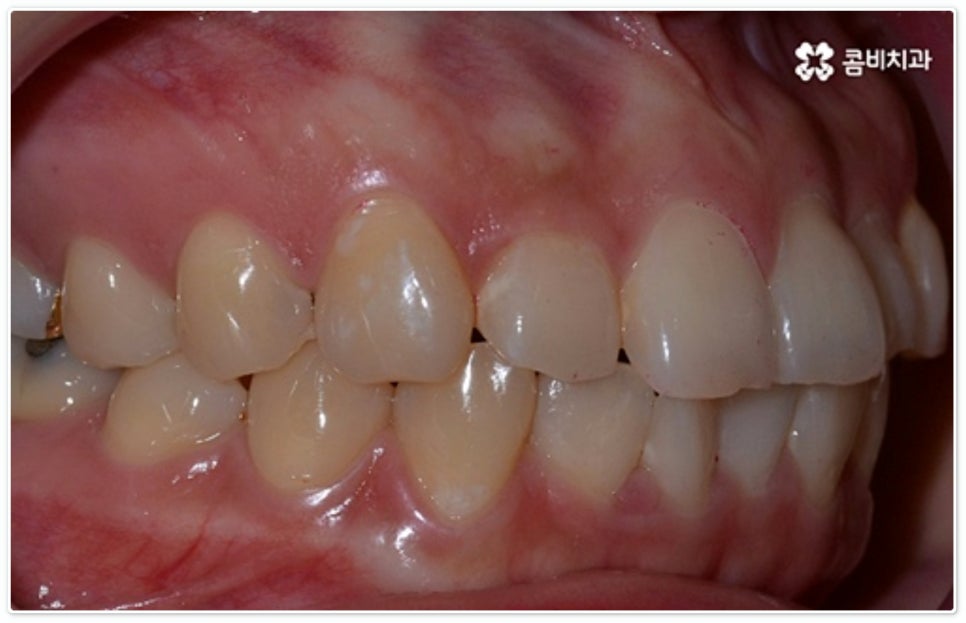

그렇지 않고 전후방 각도 조절 또는 단순 횡적인 움직임으로 치열 개선이 가능한 케이스는 부분 교정을 진행하는데, 사진에서 보시는 사례가 바로 그런 경우에 속하고 있습니다. 앞니 6개에만 브라켓을 부착하였는데 보시다시피 치아 색상과 유사한 세라믹 재질의 장치를 이용하여 심미성 또한 높여 주었음을 알 수 있어요.

토끼 앞니, 나비 앞니 중 이와 같이 어금니 교합은 정상이지만 앞니 또는 일부 치아가 돌출되거나 방향이 틀어진 경우 뿐 아니라 다른 치료 (보철 치료나 임플란트 시술) 를 위해 먼저 부분적으로 치아 이동이 필요한 경우, 교정 치료를 받은 적이 있으나 앞니 또는 주변 치아 배열이 다시 틀어진 경우 등에 있어서도 부분 교정이 이용될 수 있습니다. 그러므로 ‘치료가 오래 걸릴 것이다’, ‘장치가 보이는 게 많이 부담스럽다’, ‘재교정을 받는 것이 무섭다’ 등등 여러 걱정으로 교정 치료 시기를 미루시지 말고 필요한 경우 상담부터 차근차근 진행해 보시면 좋을 거예요.